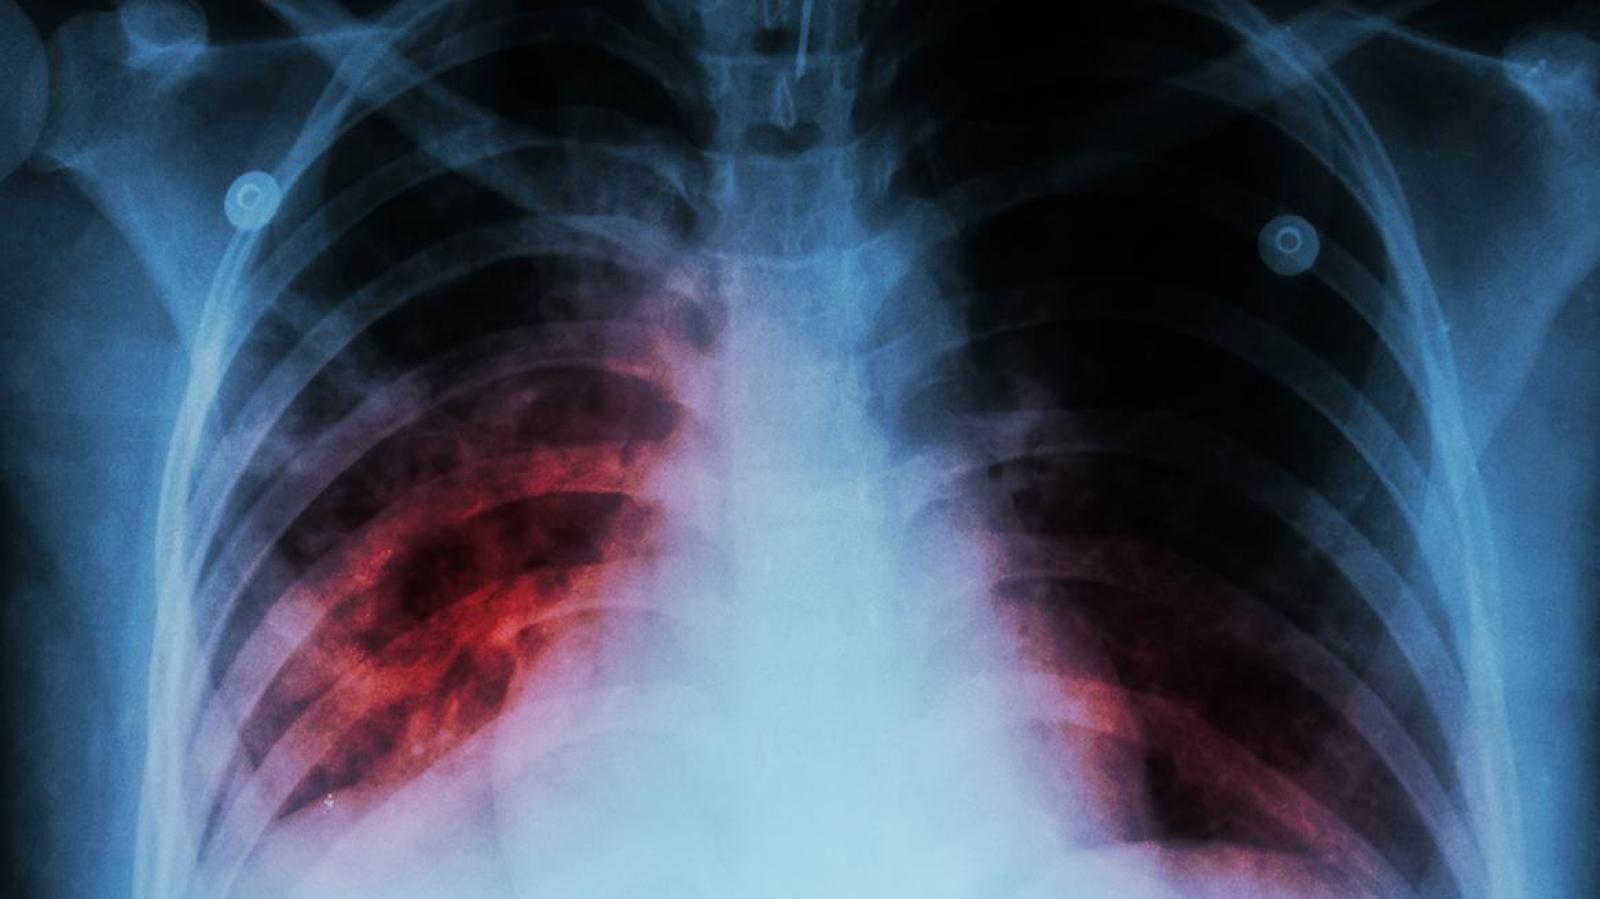

Según los Centros de control de enfermedades de Estados Unidos existen tres síntomas principales entre las personas que están desarrollando esta enfermedad: Tos intensa por 3 semanas, dolor en el pecho y tos con sangre o esputo (flema).

De igual forma, consignaron que el paciente puede sentir una pérdida de peso, fatiga, escalofríos, falta de apetito, entre otros.

Asimismo, se explicó que hay dos tipos de tuberculosis: latente y activa.

En la primera, la bacteria se encuentra en el organismo, pero está inactiva y no presenta riesgos de contagios para otras personas. Sin embargo, esta se puede convertir en una de tipo activa, la que se puede presentar días, semanas o años después de la infección.